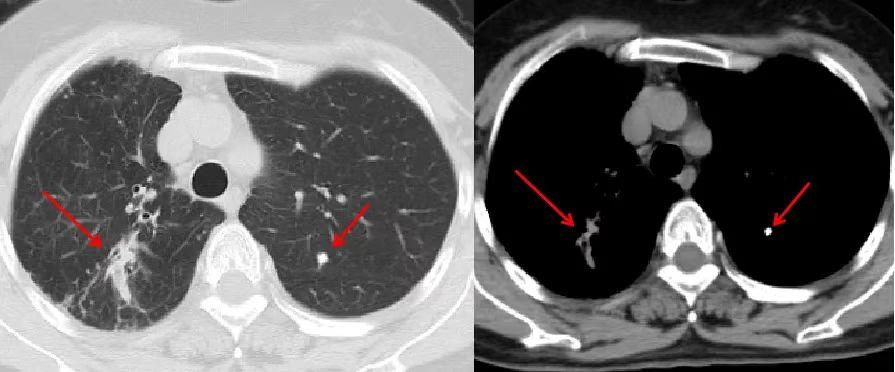

2. 胸部影像学检查:胸部X线、胸部CT,清晰显示病灶位置、范围